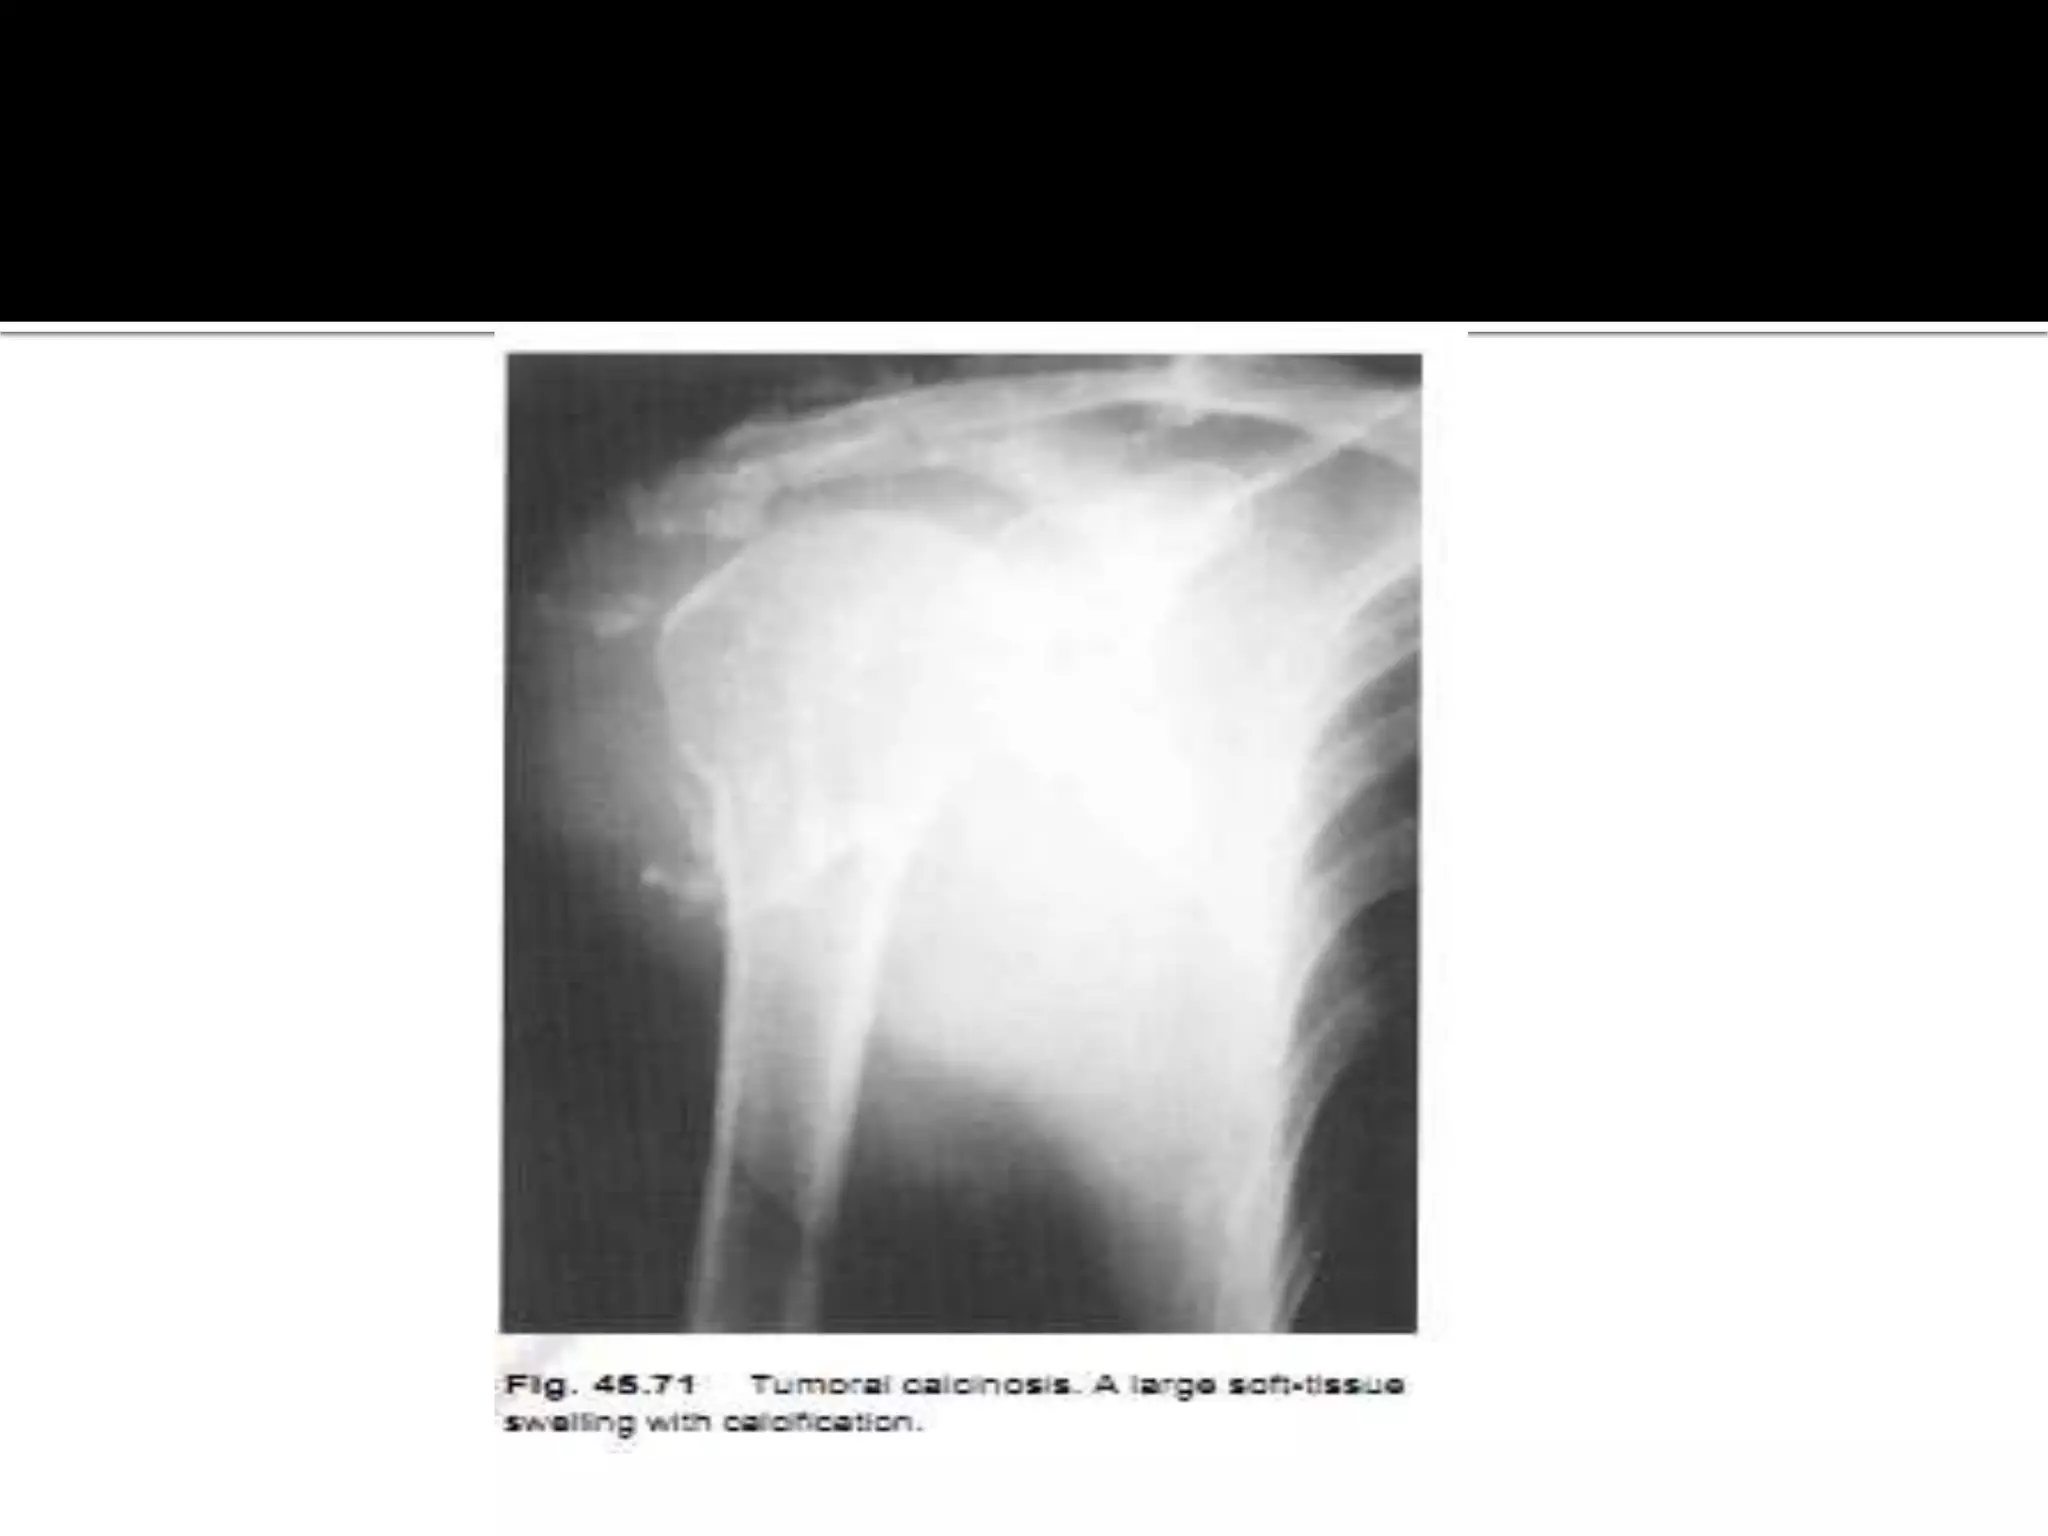

Tumoral Calcinosis

 Tumoral calcinosis typically presents in young

african men with swelling ,which may be painful,

around the large joints and predominantly affecting

the extensors surfaces.

 The hips are the most frequently involved ,followed

by the elbows and the shoulders .

• 39.

Tumoral Calcinosis  Tumoralcalcinosis typically presents in young african men with swelling ,which may be painful, around the large joints and predominantly affecting the extensors surfaces.  The hips are the most frequently involved ,followed by the elbows and the shoulders .